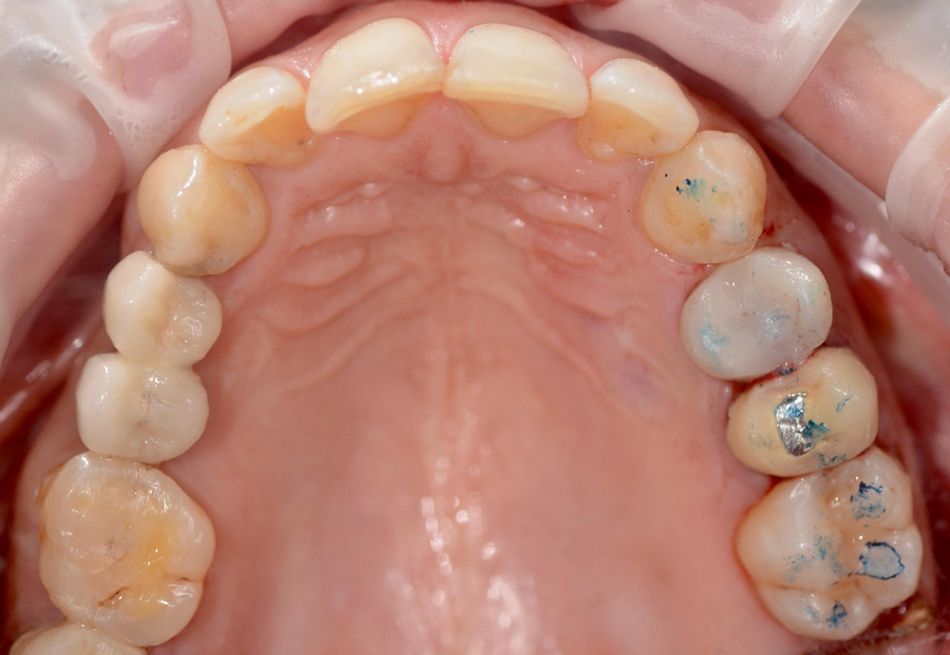

A 42-year-old female patient presented in our office with a chief complaint about a horizontal root fracture and complete crown loss of her upper left first premolar (tooth #14), compromising her aesthetics and masticatory function (Fig. 1). The patient reported to be a non-smoker, in good overall general health and displayed a history of periodontitis. Her periodontal status was assessed as stable after reinforcing hygiene routines and being included in a routine professional prophylaxis program. Oral examination revealed only a mild presence of plaque at free gingival margins and adjacent areas corresponding to a plaque index of 1, according to Silness and Löe11.

The remaining tooth root of tooth #14 was considered hopeless and unrestorable. It did not allow for a reliable and predictable long-term treatment prognosis after assessment of all, i.e., the prosthodontic, periodontal and endodontic dimensions12,13. After consideration of all potential local, site-specific and more general patient-related factors, a recommendation for implant therapy was given and was consented to by the patient.